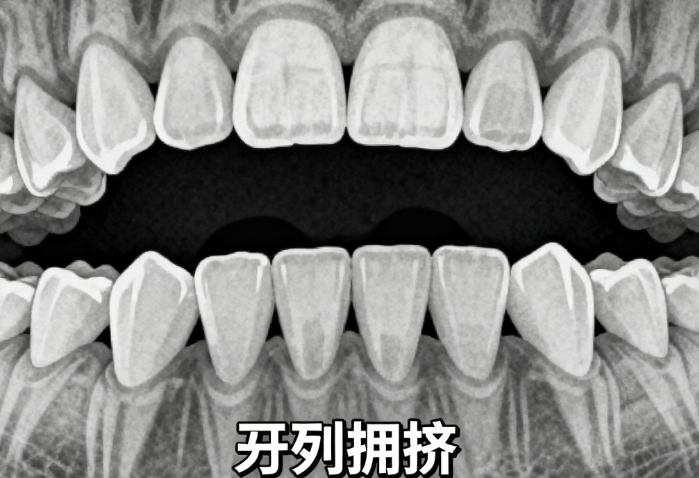

1、对于有牙齿不齐问题的患者,矫正项目是常见的选择。安康小白兔牙科提供了多种牙套方案,涵盖传统金属托槽、自锁托槽、隐形矫正等,价格和适用人群各不相同。